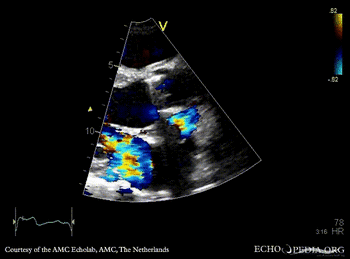

E00844.gif E00845.gif

PLAX: abscess of aortic valve prosthesis PLAX with Color Doppler: severe mitral regurgitation